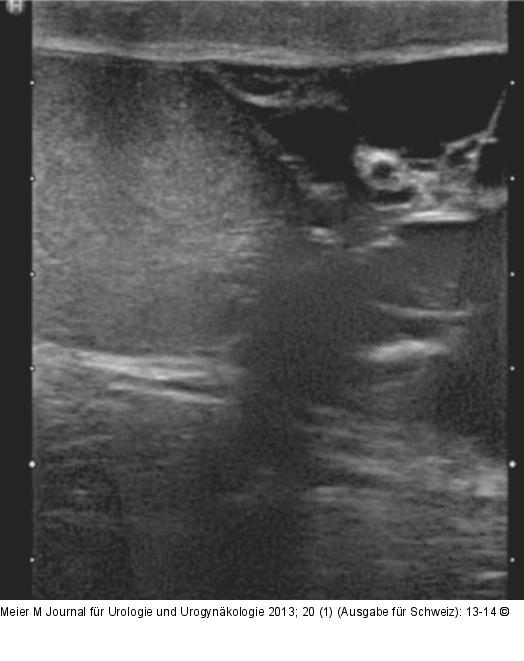

Abbildung 2: Spermatozele Sonographische Darstellung einer Spermatozele. |

Sonographische Darstellung einer Spermatozele. |